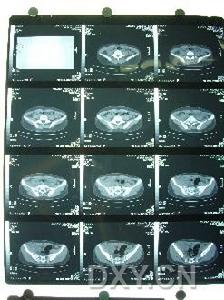

骶髂關節結核--CT主要根據其臨床表現和輔助檢查的結果,主要是X線檢查。檢查時在站立位脊柱前彎、後伸及側彎均受限,並有局部疼痛,但坐位時活動較好。臥位直腿抬高試驗,患側受限並有局部疼痛。壓擠或分離髂骨時患部疼痛,骶髂關節患部有壓痛,可有寒性膿腫或竇道。本病的輔助檢查方法主要依靠X線和CT檢查,其表現主要有以下幾個方面:

1、病變部位:骨型關節結核主要在骶髂關節前下1/3髂骨松質部。滑膜結核也可穿破關節軟骨而侵入骨組織,引起骶髂關節面及骨組織破壞。

2、骨質破壞:骨型關節結核骨破壞區呈圓形或橢圓形,破壞區邊緣可見,骶髂關節間隙無明顯狹窄。滑膜型關節結核表現為骶髂關節面不同程度的模糊或糜爛,其間隙不同程度的狹窄或增寬;有的顯示骨質明顯破壞,關節間隙不規則增寬。

骶髂關節結核--病變部位4、骨質增生硬化:骶髂關節結核無瘺管形成,未發生繼發感染亦可出現骨質增生硬化,其原因在於骶髂關節結核的骨質疏鬆常不如其他關節明顯,而往往顯示有骨質增生硬化徵象。

5、冷膿腫和竇道形成:骶髂關節結核較易發生冷性膿腫和竇道形成,多發生在臀部及腹股溝或骨盆內。